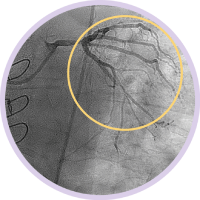

Angiography provides information on luminal characteristics of vessels, but does not provide a clear picture of the vessel and disease.

However, with IVUS guidance you can see more clearly and improve patient outcomes with informed pre-stent planning and post-stent optimization.1